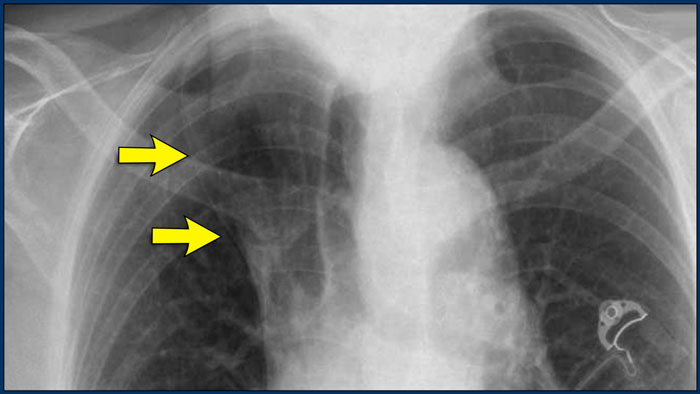

Displacement of the Azygoesophageal Line (2) – Subcarinal Lymphadenopathy

A common cause of displacement of the azygoesophageal line is subcarinal lymphadenopathy (station 7).

On the chest X-ray, note superior displacement of the azygoesophageal line just below the carina, consistent with enlarged subcarinal lymph nodes (black arrow).

Additional right paratracheal lymphadenopathy is seen, displacing the right paratracheal stripe (white arrow) and deviating the trachea to the left.

Continue with PET-CT...

PET Imaging

• PET-CT demonstrates extensive hypermetabolic lymphadenopathy in the mediastinum and neck, which is more conspicuous than on chest radiography.

• Cervical lymph nodes are involved—an important finding as they are accessible for biopsy.

Continue with images of CT and ultrasound...

CT Imaging

• Contrast-enhanced CT shows bulky subcarinal lymphadenopathy displacing the azygoesophageal recess and compressing the left atrium.

• Biopsy of a cervical node confirmed small cell lung carcinoma.